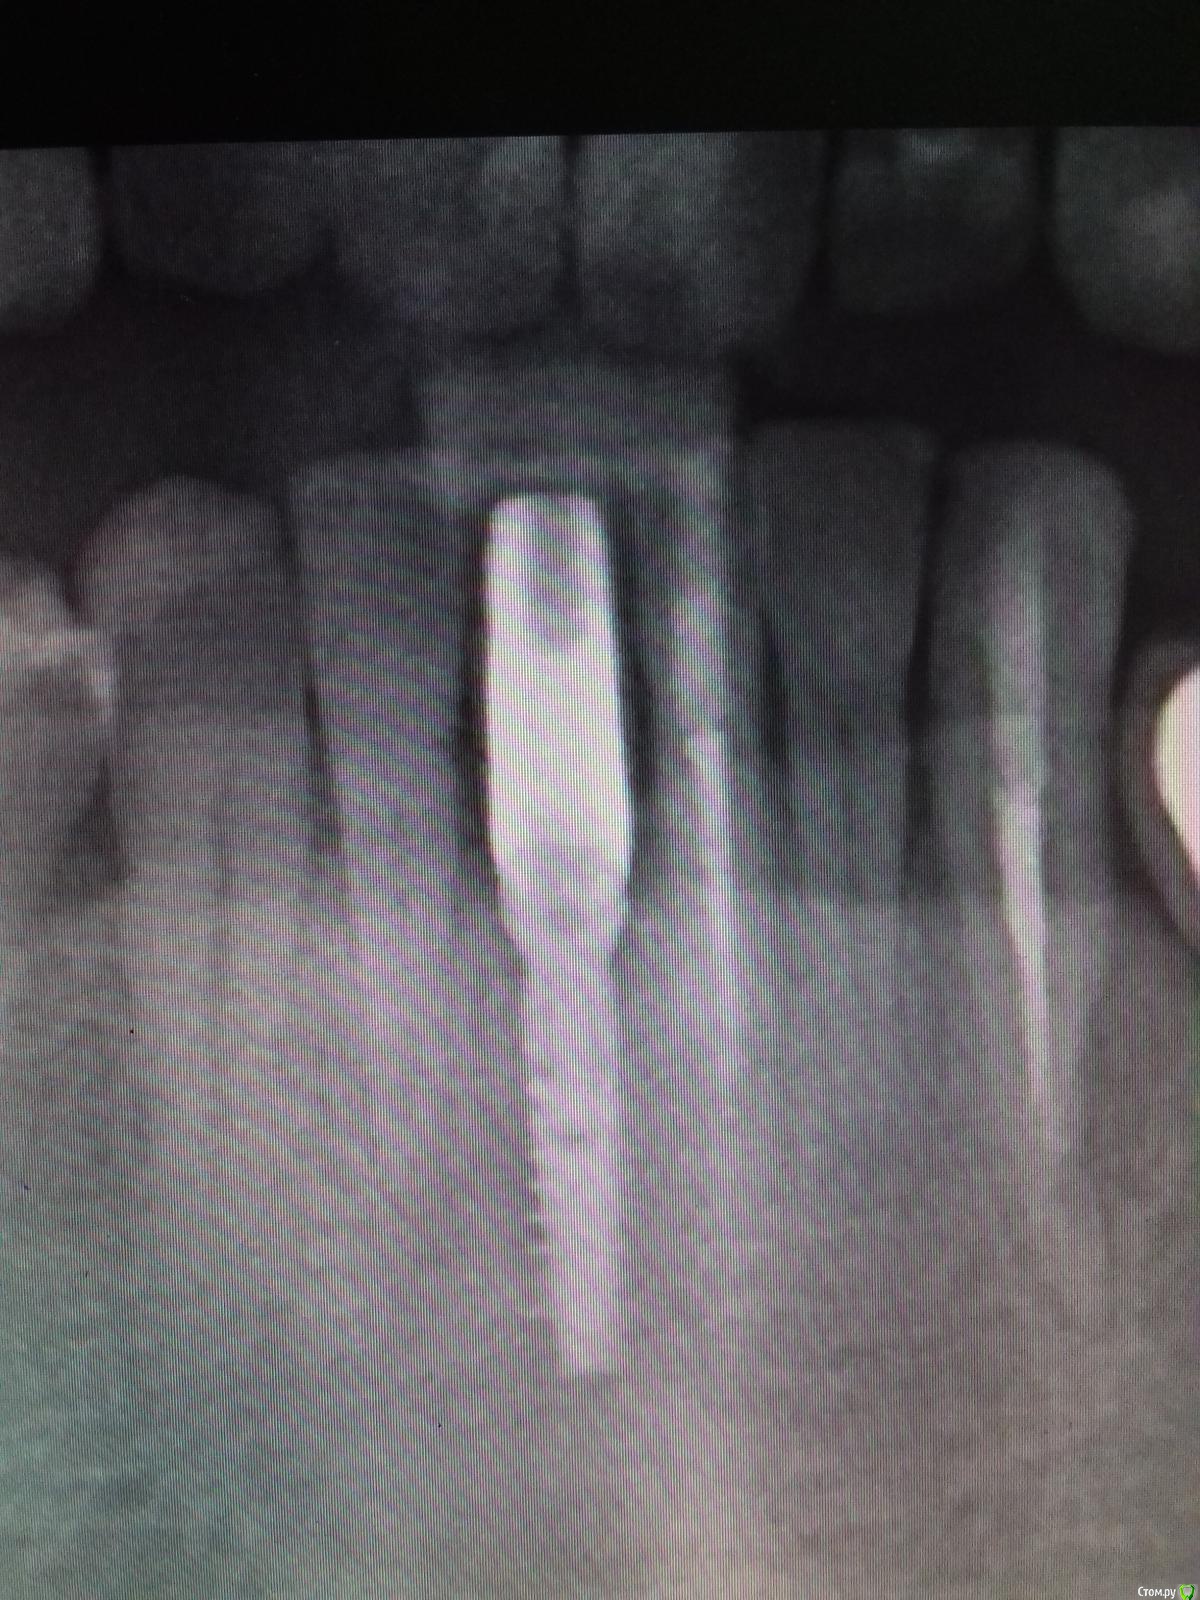

Jurai Опубликовано 25 декабря, 2016 Поделиться Опубликовано 25 декабря, 2016 *Предупреждение: фото на "мыльницу", не все этапы удались, но я работаю над этим) Вот пациент. Приятнейший, во всех отношениях, с негативным отношениям к мостовидным конструкциям. Полтора года лечил 41з по поводу периодонтита: толку не вышло. Удалил у широко известного многим стоматологам, особенно выпускам последних годов, доктора с ученой степенью. После удаления 4 месяца, по КТ область вполне достойно выглядит. Вот с чем пришел, обычное дело, все прилично: Раскрываю, а там между тонкими кортикалками мягко и упруго - резидуальная, фото нет. Открываю сильнее чем обычно, с расстройства не особо удачно. Кюретаж : Вид после, ушла вестибулярная кортикальная вместе с кистой: Сверлим 2,0, позиционердля рентген-контроля Имплантат ADIN UNP2,75Х11,5мм Ауто, джейсон коллагенфлис (что было под рукой) Швы. Контроль, перещелкивать не стали. В общем, понравился имплантат, для себя пометку кюретажить тщательнее, не надеяться, что организм все переварит. 1 9 Ссылка на комментарий

Jurai Опубликовано 24 января, 2018 Автор Поделиться Опубликовано 24 января, 2018 Год спустя, 9 месяцев после протезирования. 1 7 Ссылка на комментарий

Jurai Опубликовано 15 марта, 2024 Автор Поделиться Опубликовано 15 марта, 2024 Рекол! 7 лет в нагрузке. Нужно уточнить, что у пациента кошмарный прикус, 3 класс. 10 1 2 Ссылка на комментарий